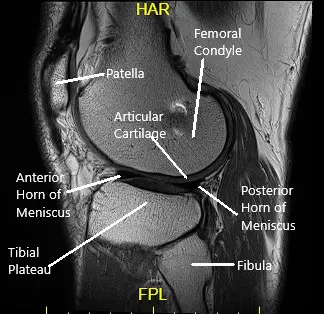

She had an MRI which showed tearing of the medial meniscus at the meniscocapsular junction and posterior horn-body junction. There was tri-compartmental cartilage loss.

Sagittal MRI view of the left knee.